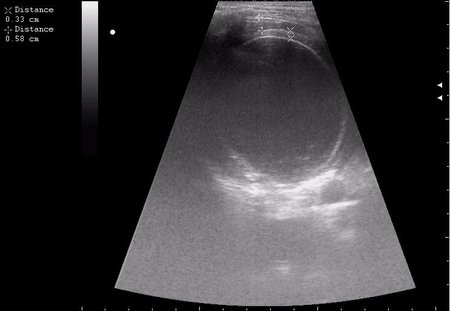

спустя 8 мес. после операции